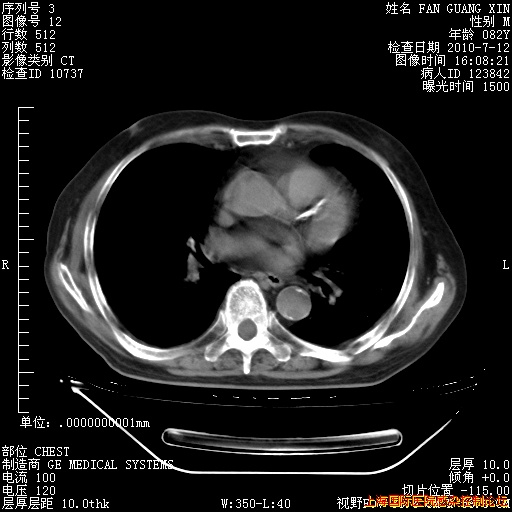

6月12日肺窗

6月12日纵膈窗

整整相隔30天的肺部CT好像有所好转啊。甲强龙减量第3天,需要观察体温。